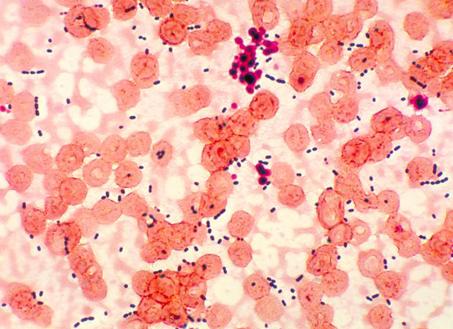

Энтерококки – грамм-положительные кокки, которые относятся к подклассу лактобактерий.

Обычно микроорганизмы такого вида размещаются либо парами, либо же короткими цепочками. Ранее этих бактериальных агентов относили к стрептококкам, но в 1984 году учёные решили сделать их отдельным рядом.

Энтерококки (лат. Enterococcus) – это род шарообразных или слегка вытянутых, грамположительных бактерий семейства Энтерококковые (Enterococcaceae). Размещение обычно происходит парами (диплококки) или же короткими цепочками.

По физиологическим характеристикам энтерококки очень схожи со стрептококками, в связи с чем, изначально, до 1984 года, этот вид бактерий относили к стрептококковой инфекции.

По состоянию на 2017 год, к энтерококкам причислено 15 видов бактерий, наиболее популярными из которых являются – энтерококк фекальный (Enterococcus faecalis) и энтерококк фэциум (Enterococcus faecium), которые также выступают в качестве симбиотических микроорганизмов кишечника человека.

Энтерококки представляют собой круглые или слегка овальные, грамположительные, факультативные анаэробы, размером 0,6–2,0 на 0,6–2,5 мкм, для размножения и жизнедеятельности которых достаточно как большое, так и малое количество кислорода. Рост и развитие этого вида бактерий происходит за счет энергии брожения, при температуре 10-45 °С. Наиболее же оптимальной температурой окружающей среды для наилучшего размножения инфекции является 35-37 °С.